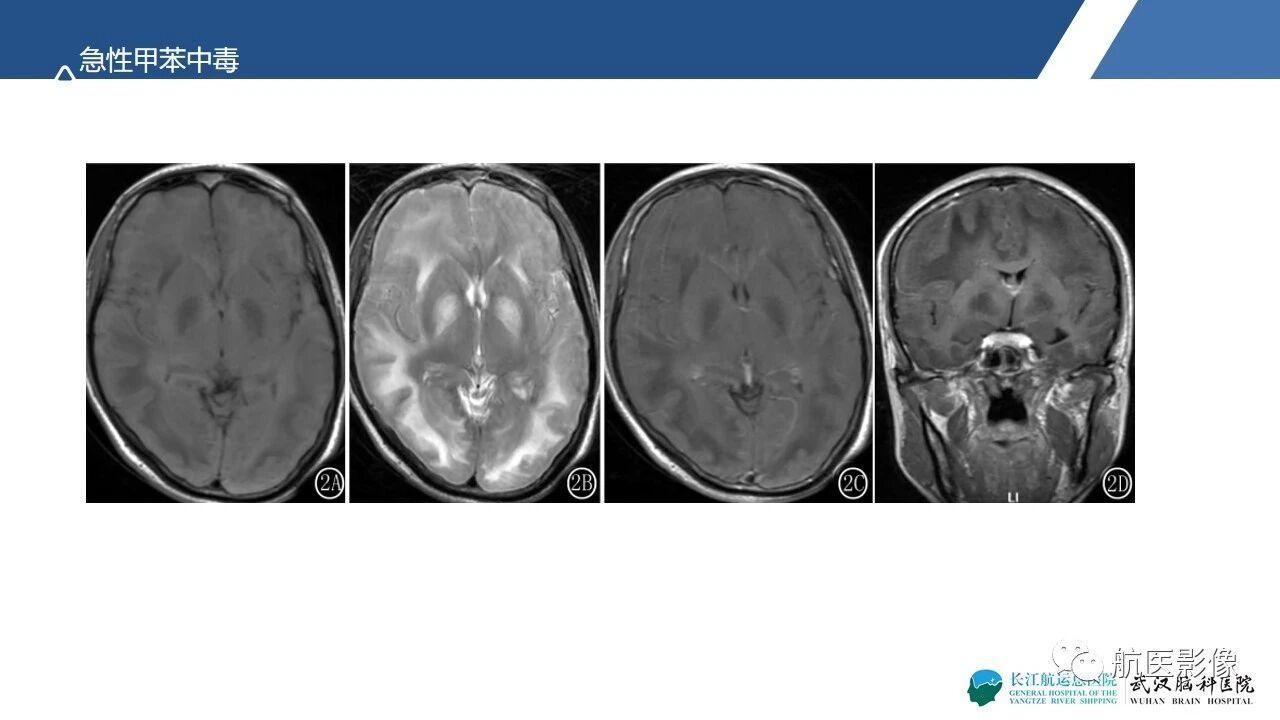

基底节区、丘脑对称性病变影像表现